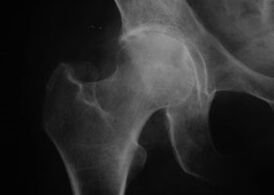

Aspetto di un'articolazione con artrosi

Coxatrosi, artrosi dell'articolazione dell'anca

Con questa malattia si osserva un quadro clinico classico dell'artrosi.

Il primo sintomo della coxartrosi è il disagio all'articolazione dell'anca dopo l'attività fisica.

Con la coxartrosi progressiva compaiono aumento del dolore, rigidità e mobilità limitata.

I pazienti affetti da una forma grave di coxartrosi risparmiano l'arto colpito, evitando di calpestarlo e, da fermi, scelgono posizioni in cui il dolore è minimo.